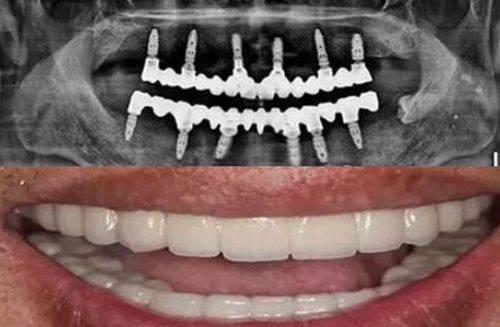

第四类是牙周情况复杂需要进行深度治疗的女性,比如需要同时进行龈下刮治、根面平整、牙周手术等操作的人群,这些治疗对口腔组织的损伤较大,经期进行会大幅增加出血和感染的风险,完全地不建议在经期进行。这类深度牙周治疗通常需要多次就诊,完全可以避开经期安排治疗时间。